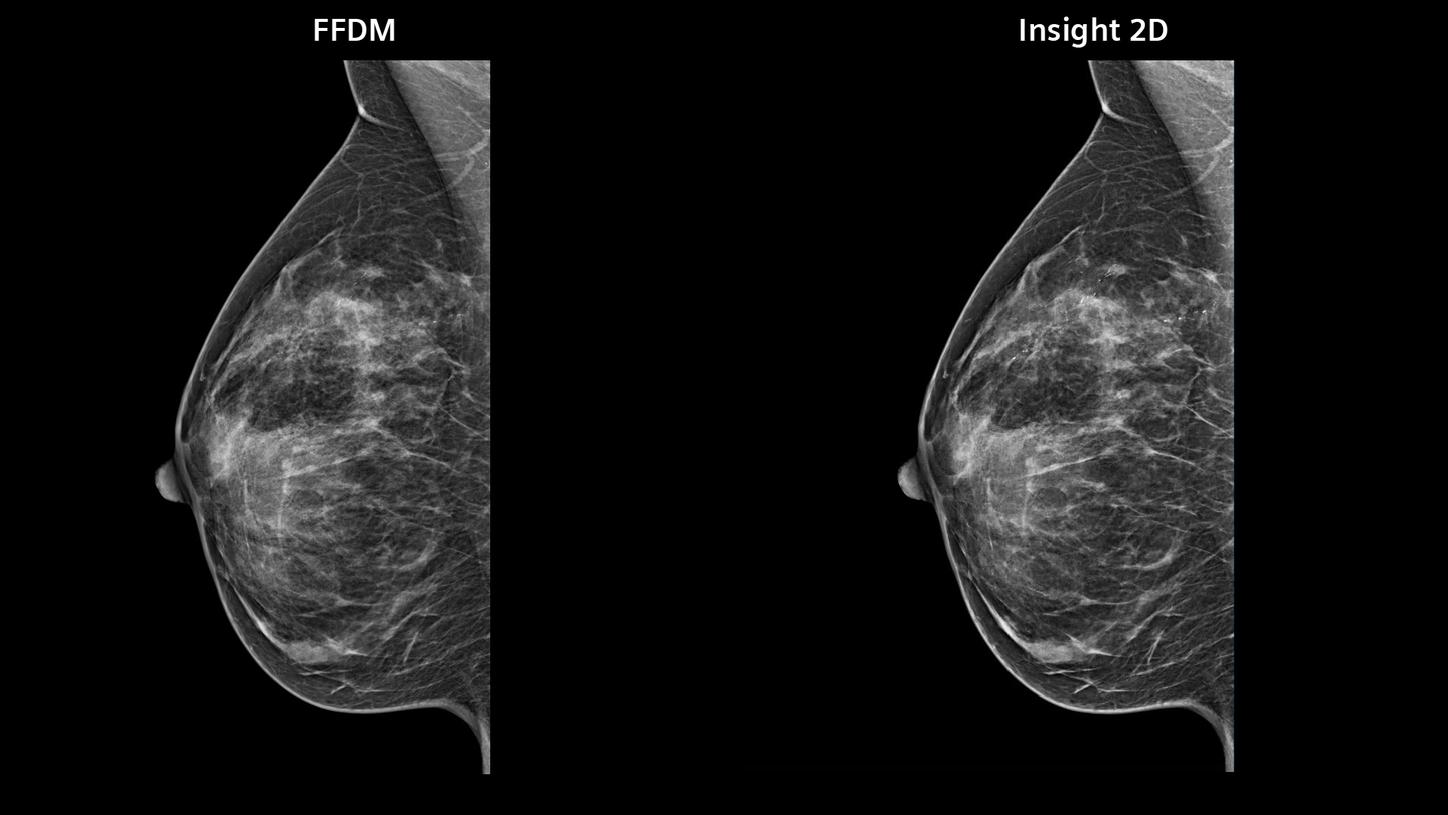

Synthetic imaging

Synthesized 2D mammographic imaging (Insight 2D) and unique, rotating synthesized

3D mammographic imaging (Insight 3D)